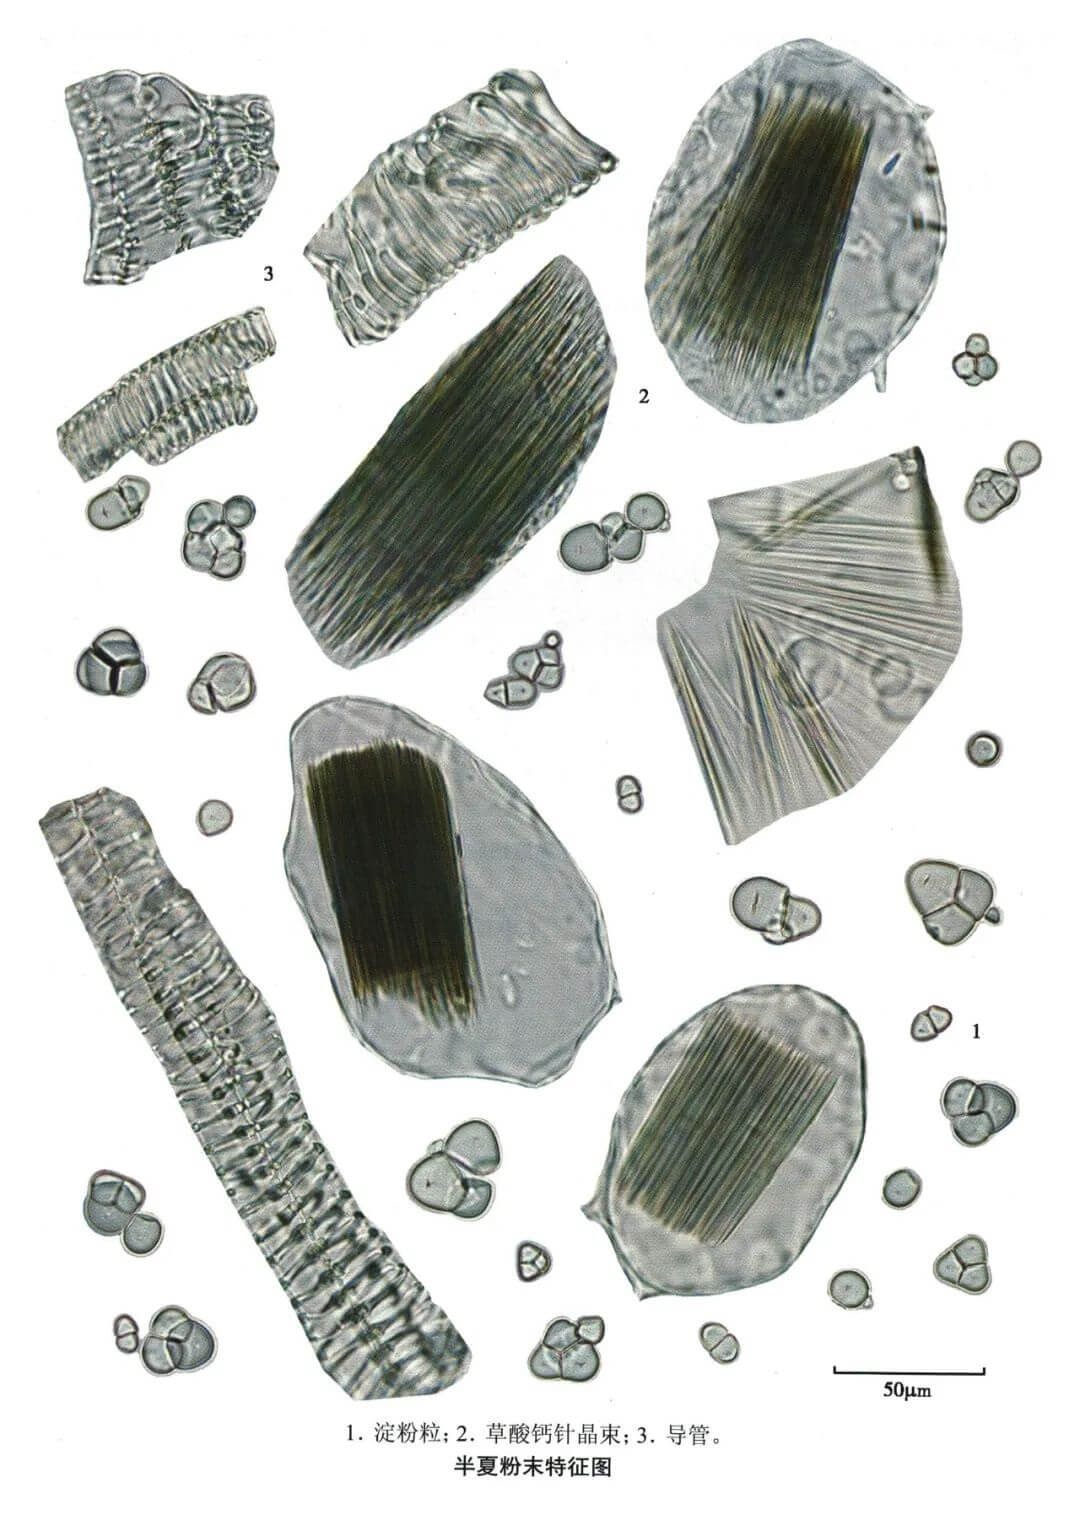

半夏

| 半夏 |

|---|

| 【参考标准】 《中国药典》2020年版一部 |

| 【显微鉴别】 本品粉末类白色。淀粉粒甚多,单粒类圆形、半圆形或圆多角形,直径2~20μm,脐点裂缝状、人字状或星状;复粒由2~6分粒组成。草酸钙针晶束存在于椭圆形黏液细胞中,或随处散在,针晶长20~144μm。螺纹导管直径10~24μm。 |

| 【显微重点】 草酸钙针晶束存在于椭圆形黏液细胞中。 |

| 【图谱来源】 《中药成方制剂显微图典》 |